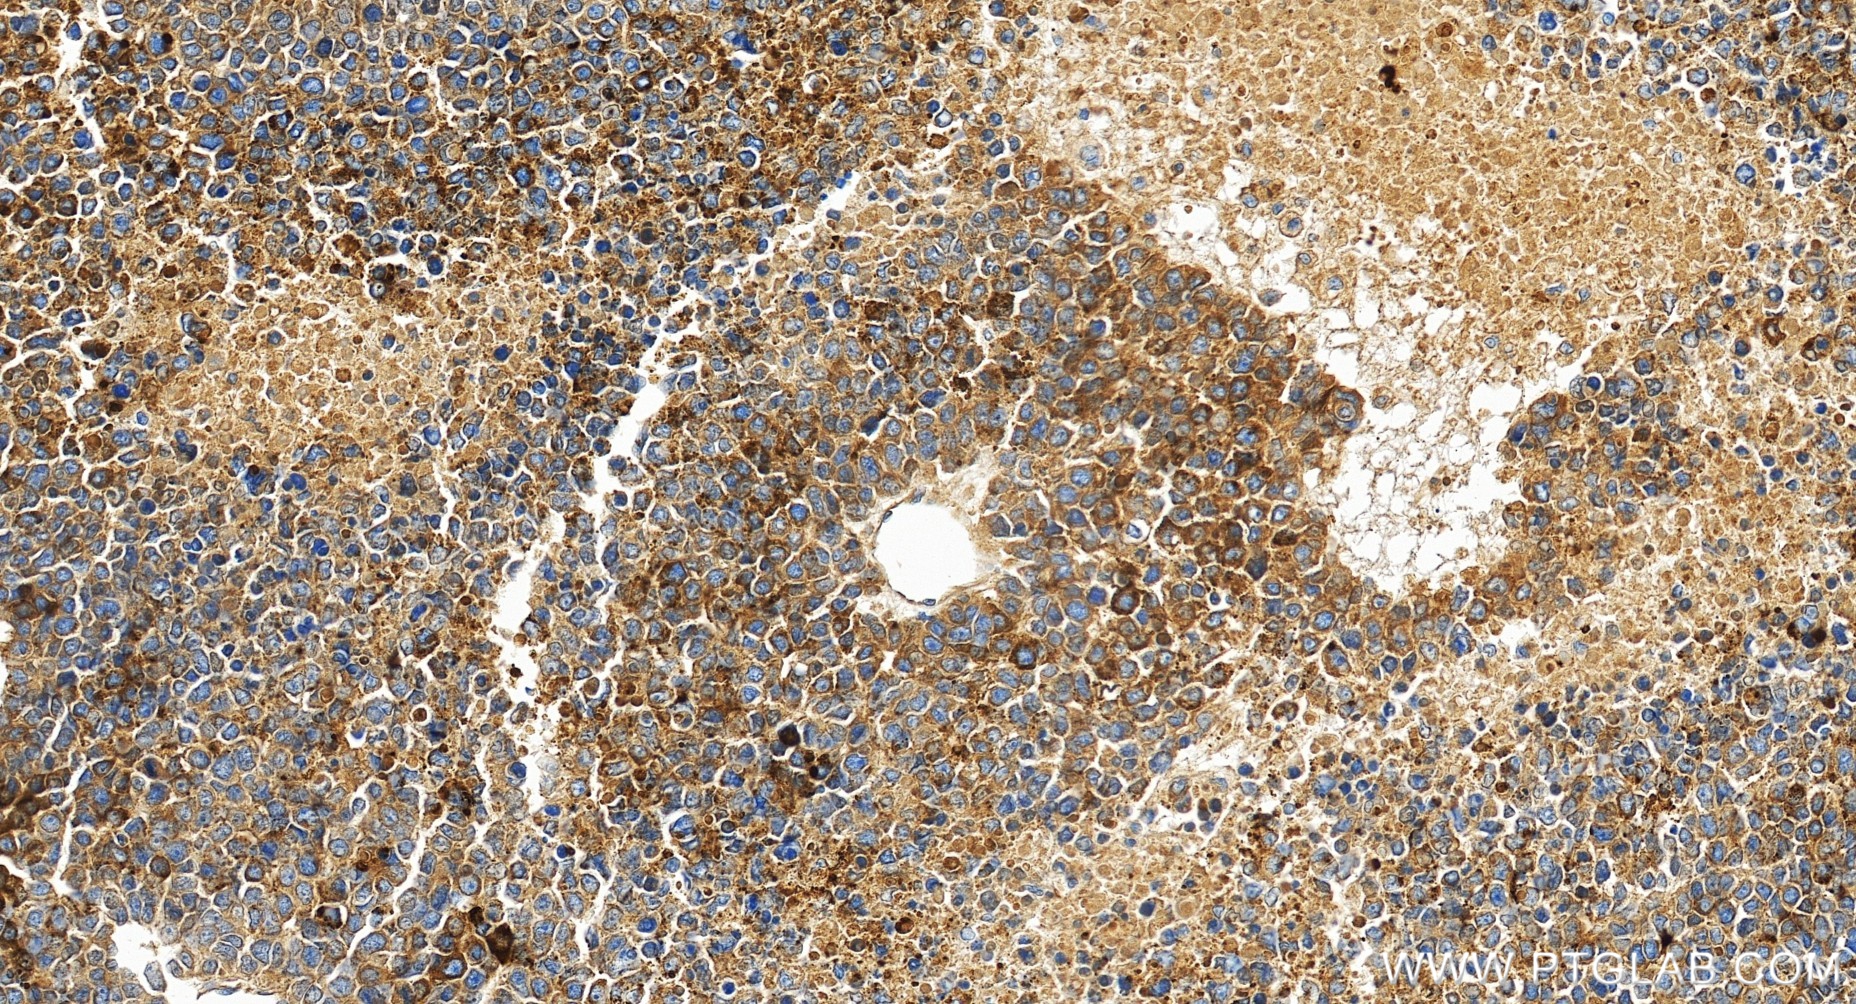

| Positive IHC detected in | human liver cancer tissue, human liver tissue Note: suggested antigen retrieval with TE buffer pH 9.0; (*) Alternatively, antigen retrieval may be performed with citrate buffer pH 6.0 |

| Immunohistochemistry (IHC) | IHC : 1:500-1:2000 |

82982-6-RR targets AFP in WB, IHC, ELISA applications and shows reactivity with human samples.

AFP (Alpha-fetoprotein) is a major plasma protein in the fetus and its concentration is very low in the adult (PMID:24120489). AFP can be detected at abnormally high concentrations in hepatocellular carcinomas as well as in the plasma and ascitic fluid of adults with hepatoma, indicating that AFP can serve as a tumor marker (PMID: 18669658). AFP is also a glycosylated protein and based on its binding capability to lectin Lens Culinaris Agglutinin (LCA), and total AFP can be separated into three different glycoforms, AFP-L1, AFP-L2, and AFP-L3. Core-fucosylated form of AFP (AFP-L3) is a more specific indicator than total AFP for HCC (PMID: 33128033, 35458505)